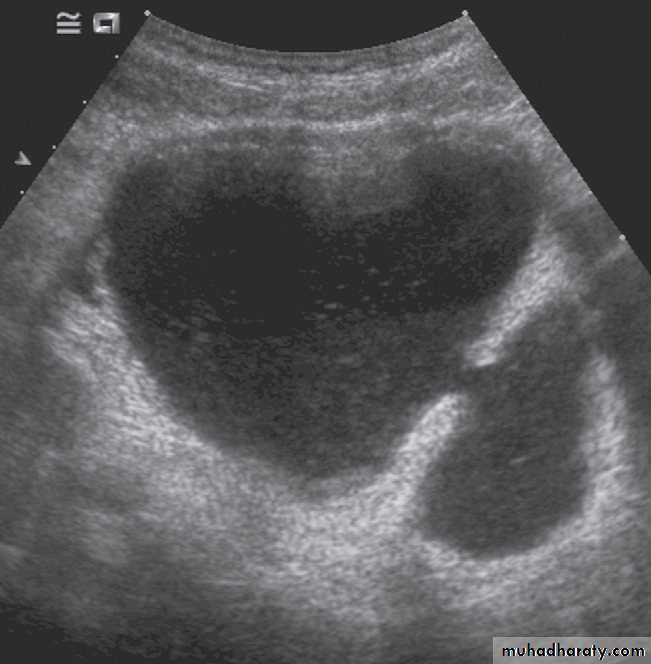

The bladder is the most frequent site for neoplasms in the urinary tract . Almost all are transitional cell carcinomas of varying degrees of malignancy.On ultrasound examination

bladder tumours are seen as soft tissue masses protruding into the fluid-filled bladder or as localized bladder wall thickening, . On rare occasions, there is visible calcification on the surface of the tumour, but the technique is poor for detecting extravesical spread.